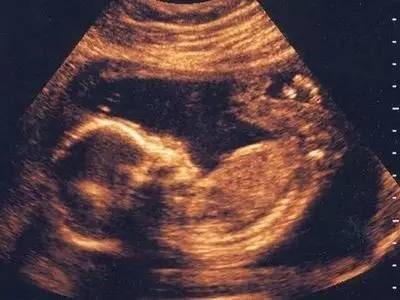

胎儿在出生前几周已经会哭会笑。科学家已经通过4D超声波发现,胎儿在即将出生前已经大哭过了。相对的情绪反应微笑,在胎儿即将离开母体之前也已学会。